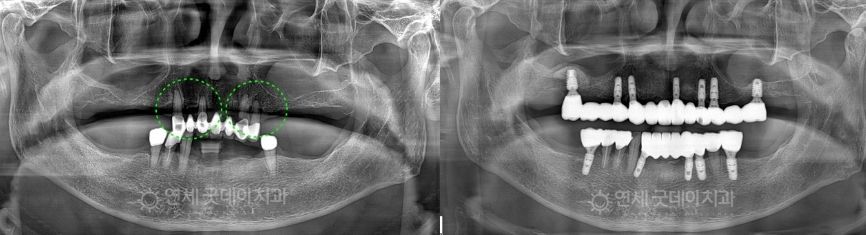

如果每一個缺牙空隙都植入植體,治療費用將成為沉重的經濟負擔。

即使是在大多數牙齒缺失、看似需要全口植牙的情況下,

我們也僅會在

必要的位置 植入植體,

再透過牙橋等贋復物連接,

即可達到穩定、經濟,且咀嚼能力接近自然牙的治療效果。

這就是為什麼我們會根據患者的口腔狀況及多種個別因素,

來尋找合理、可行的治療方案。

Case Review

Full Mouth Implant Before & After